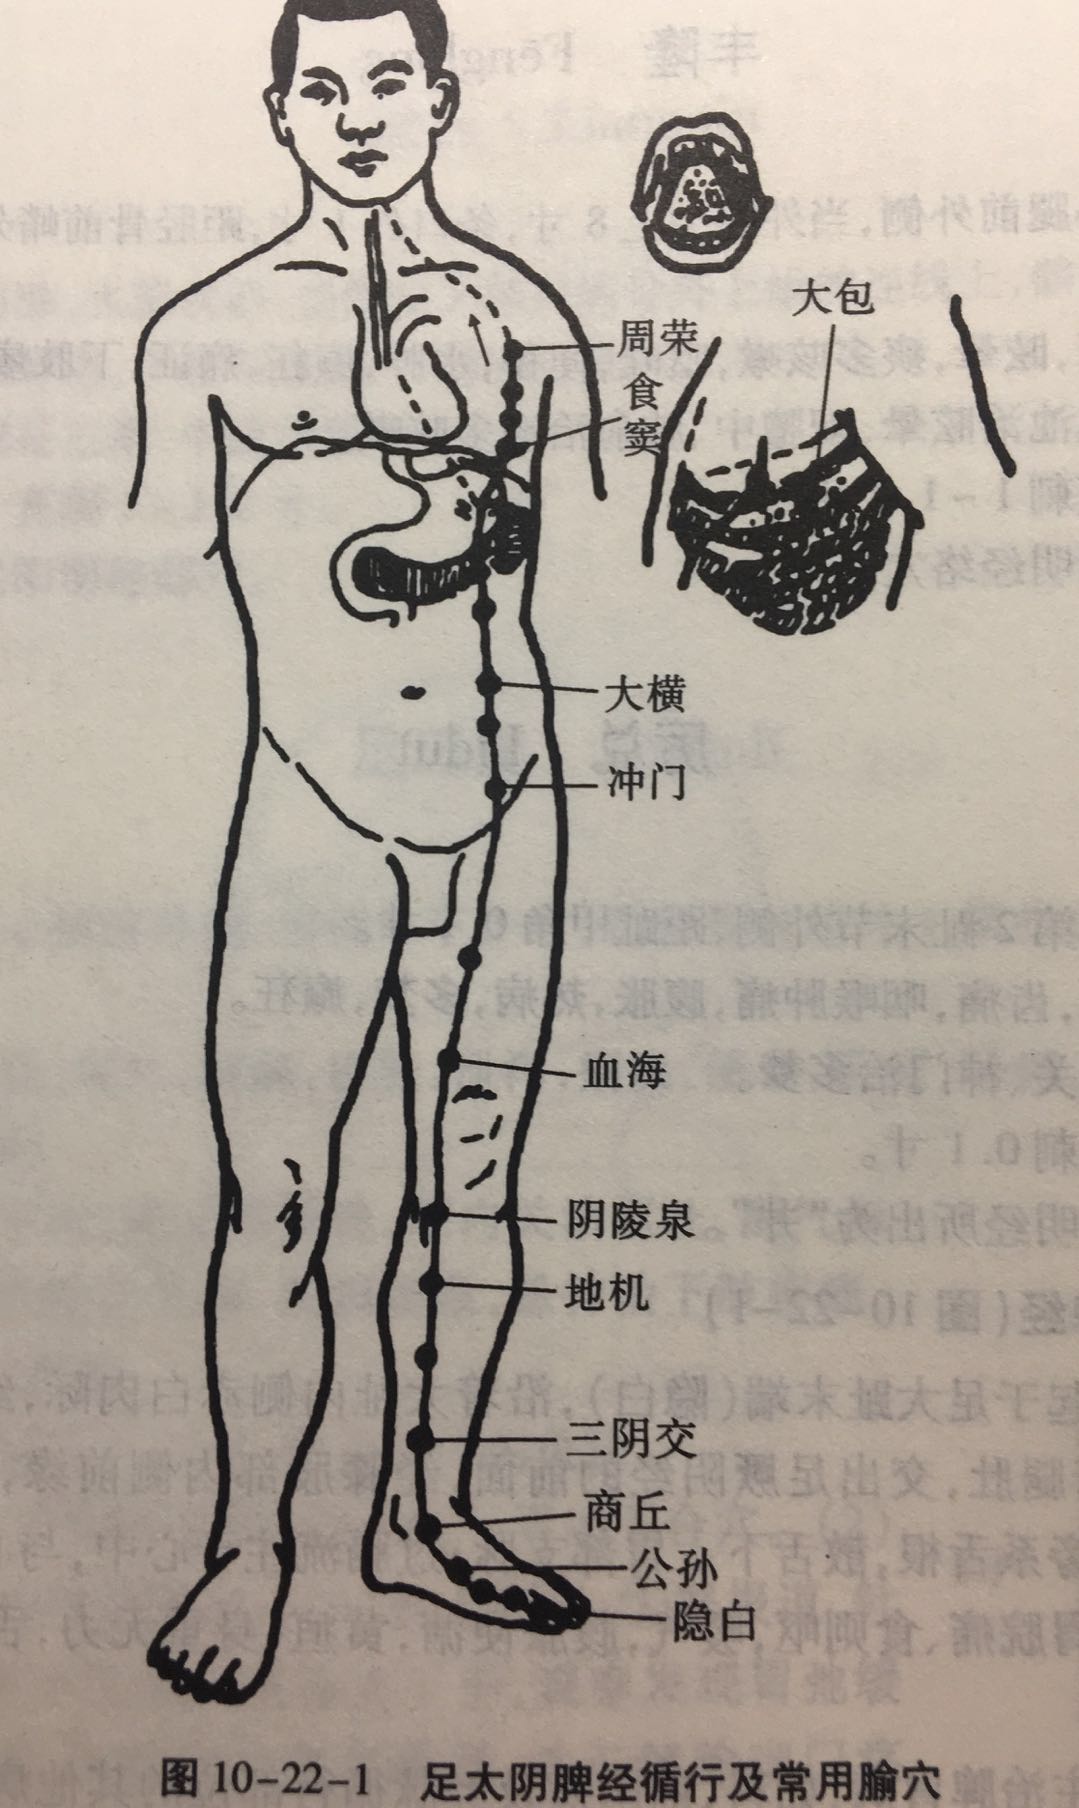

【(四)足太阴脾经(图10-22-1)】

1、时辰 巳时 9 ~ 11

2、歌诀 足太阴脾由足拇,隐白先从内侧起,大都太白继公孙,商丘直上三阴交,漏谷地机阴陵泉,血海箕(jī)门冲门前,府舍腹结大横上,腹哀食窦(dòu)天溪连,胸乡周荣大包尽,二十一穴太阴全。

3、经脉循行 起于足大趾末端(隐白),沿着大趾内侧赤白肉际,经第一跖(zhí)趾关节向上行至内踝前,上行腿肚,交出足厥阴经的前面,经膝股部内侧前缘,进入腹部,属脾络胃,过膈上行,夹咽旁系舌根,散舌下。

胃部支脉:过膈流注于心中,与心经相接。

从大趾末端开始(隐白穴),沿大趾内侧赤白肉际(大都穴),经核骨(第一骨小头后(太白穴、公孙穴),上向内踝前边(商丘穴),上小腿内侧,沿胫骨后(三阴交穴、漏谷穴),交出足厥阴肝经之前(地机穴、阴陵泉穴),上膝股内侧前边(血海穴、箕门穴),进入腹部(冲门穴、府舍穴、腹结穴、大横穴;中极穴、关元穴,属于脾,络于胃(腹哀穴;会下脘穴、日月穴、期门穴),通过膈肌,夹食管旁(食窦穴、天溪穴、胸乡穴、周荣穴;络大包;会中府穴),连舌根,散布舌下。

它的支脉:从胃部分出,上过隔肌,流注心中,接手少阴心经。

4、主要病候 胃脘痛、食则呕,嗳气,腹胀便溏,黄疸,身重无力,舌跟强痛,下肢内侧肿胀,厥冷。

5、主治概要 主治脾胃病,妇科,前阴病及经脉循行部位的其他病证。

隐白

【定位】 在足大趾末节内侧,距趾甲角 0.1 寸(图 10-22-2)。

【主治】 腹胀,便血,尿血,月经过多,崩漏,癫狂,多梦,惊风。

【配伍】 配地机、三阴交治疗出血症。

【刺灸法】 浅刺 0.1 寸。

【附注】 足太阴经所出为“井”。

公孙

【定位】 在足内侧缘,当第 1 跖骨基底部的前下方(图 10-22-2)。

【主治】 胃痛,呕吐,腹痛,泄泻,痢疾。

【配伍】 配中脘、内关治胃酸过多、胃痛。

【刺灸法】 直刺 0.6 ~ 1.2 寸。

【附注】 足太阴经络穴:八脉交会穴之一,通于冲脉。参考资料:①据报道,对消化性溃疡病人进行 X 线胃肠检查时,观察到针刺内关、足三里对胃蠕动多有增强作用,尤以足三里为明显,而针刺公孙则胃蠕动多减弱。②据报道,针刺公孙、内关、梁丘等穴有抑制胃酸分泌作用。

三阴交

【定位】 在小腿内侧,当足内踝尖上 3 寸,胫骨内侧缘后方(图 10-22-3)。

【主治】 肠鸣腹胀,泄泻,月经不调,带下,阴挺,不孕,滞产,遗精,阳痿,遗尿,疝气,失眠,下肢痿痹,脚气。

【配伍】 配足三里治肠鸣泄泻,配中极治月经不调,配子宫治疗阴挺,配大敦治疝气,配内关、神门治失眠。

【刺灸法】 直刺 1 ~ 1.5 寸。

【附注】 (1)足太阴、少阴、厥阴经交会穴。(2)孕妇禁针。

血海

【定位】 屈膝,在大腿内侧,髌(bìn)骨内上缘上 2 寸,当股四头肌内侧头的隆起处(图 10-22-4)。

简便取穴:患者屈膝,医者以左手掌心按于患者右膝髌骨上缘,2 至 5 指向上伸直,拇指约呈 45 度斜置,拇指尖下是穴。对侧取法仿此。

【主治】 月经不调,崩漏,经闭,瘾疹,湿疹,丹毒。

【配伍】 配三阴交治月经不调,配曲池治瘾疹。

【刺灸法】 直刺 1 ~ 1.5 寸。